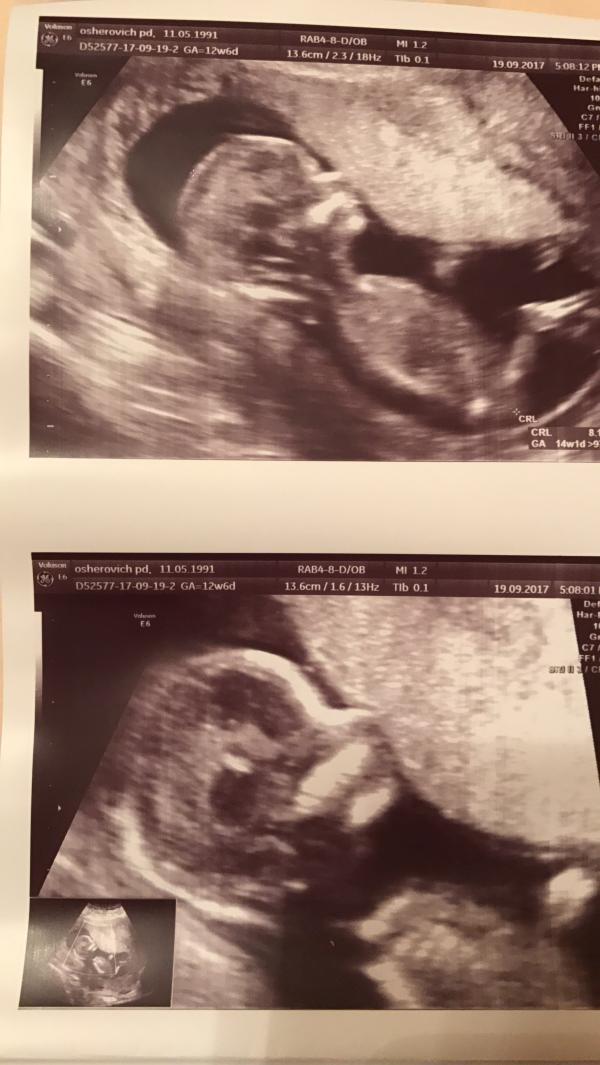

Сходили на первый скрининг, сначала платно, в центр медицины плода на секейроса к врачу Овинцевой, все очень понравилось, смотрели полтора часа, все досконально 👌👌👌 даже пол смогла разглядеть! Врач 👨⚕️ хороший и внимательный. Оказалось в консультации поставили настолько не верный срок и я не успела сдать кровь на скрининг, а об этом я даже от своего врача в консультации и не слышала к сожалению. На следующий день пошли на скрининг в свою консультацию, смотрели меня меньше 5 минут, ребёнка показали на секунду ( вот голова, вот ноги) ни фото, ни намёка на определение пола там сделано не было. У врача я там была минут 10 в общей сложности. Вообщем разочаровалась очень в бесплатной медицине, прям очень 🤷♀️ как можно было проворонить сдачу крови, до сих пор не понимаю, сказали бы я платно хоть сдала бы. Теперь назначили через неделю скрининг на 2 триместре.

Центр медицины плода ,наверное для меня самый лучший центр))